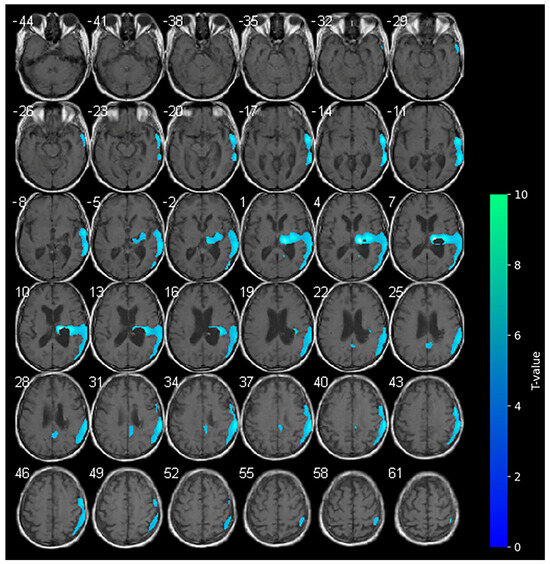

3.2. 18F-FDG-PET and Anodal-tDCS (T1)

Marked hypometabolism of the right hemorrhagic nucleo-capsular lesion persisted, but interestingly, a reduction in the extension of hypometabolic areas was noted compared with the baseline in the right frontal and parietal cortices. Furthermore, an increase in the uptake of the tracer was detected in the contralateral non-stimulated hemisphere (Figure 2).

During anodal tDCS, consistent with the reported data in the literature, the diffuse areas of hypometabolism observed in the affected hemisphere at the baseline were diffusively reduced, resulting in increased metabolism in these areas. In contrast with the main hypothesis of anodal tDCS functioning, the increase in metabolism in the contralateral unaffected hemisphere during anodal tDCS was unexpected.

At the second evaluation, a slight improvement was noted in cognitive functioning, as evidenced by an increase in the LCF score to 6. The responses to elementary commands demonstrated a greater degree of consistency, and the commencement of complex tasks was observed, albeit with significant delays and a certain degree of confusion. A greater degree of self-awareness was evident, accompanied by appropriate behavior. However, the subject exhibited severe impairments in recent memory and cognition, as evidenced by impaired performance in problem-solving tasks and judgment. Globally, no significant changes were observed in neurological severity or functional status as the NIHSS, mRS, and MI scores did not change.

The present findings appear to corroborate extant hypotheses concerning the effects of tDCS on patients with stroke [31], but concurrently provide new insights. In our study, we report unexpected brain metabolism in the contralateral hemisphere determined by anodal tDCS. According to the literature, during anodal-tDCS, the widespread areas of hypometabolism observed in the affected hemisphere at the baseline were significantly reduced (see Figure 1), indicating a global increase in the metabolism within the affected hemisphere. The increase in brain metabolism of the contralateral unaffected hemisphere during anodal-tDCS of the affected hemisphere is instead quite unexpected. It is possible that the stimulation of the affected hemisphere conversely modulates anatomical and functional networks activating the contralateral hemisphere [32,33]. The clinical improvements observed in our patient could be related to the reduction in hypometabolic areas in the affected hemisphere following anodal-tDCS, also suggesting the restoration of neuronal activity function in regions previously suppressed due to stroke-related damage. The unexpected increase in metabolism in the contralateral (unaffected) hemisphere may be indicative of a compensatory or network-level reorganization process, in which stimulation of the affected primary motor cortex influences functionally connected regions across hemispheres [11], thereby highlighting the distributed nature of neuroplastic responses to tDCS.

Figure 2. SPM analysis results (t-maps) during anodal-tDCS. The red and blue areas indicate voxels of significantly increased and reduced metabolism in comparison to the normal control subjects, respectively (p > 0.001).